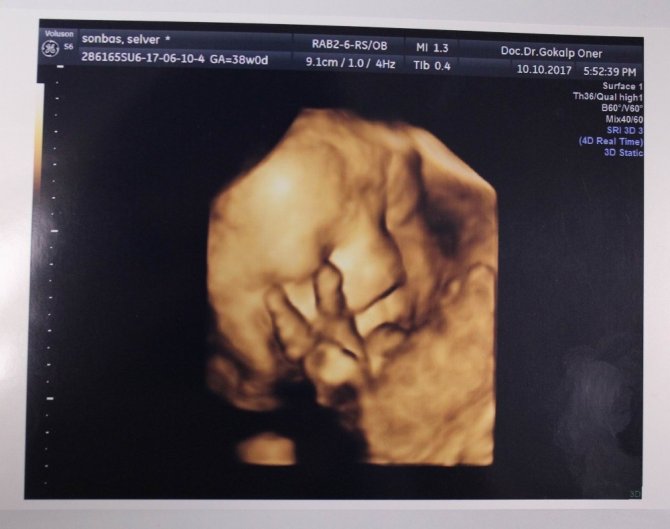

Anne karnındaki bebeklerin çekildiği dört boyutlu ultrason fotoğraflara takılan pozlar bazen şaşırtıyor. Henüz 22 haftalıkken zafer işareti yapan bebeğin fotoğrafı bunlardan en ilgi çekici olanı.

Memorial Kayseri Hastanesi Kadın Hastalıkları ve Doğum Uzmanı Doç. Dr. Gökalp Öner'in yaklaşık 2 yıldır çektiği 400'ün üzerinde, dört boyutlu ultrason fotoğraflara takılan anne karnındaki bebeklerin ilginç pozları dikkat çekiyor. Zafer işareti yapan, burnunu karıştıran, dilini çıkaran, uzun hava çeken, düşünen bebek fotoğrafları ebeveynleri hem mutlu ediyor hem de şaşkınlığa uğratıyor.

Mutlu geçirilmesi gereken hamilelik dönemini bu fotoğraflarla renklendirdiklerini dile getiren Doç. Dr. Gökalp Öner, "Bu fotoğraflarda bazen ilginç pozlar yakalıyoruz. Bebeklerimiz ağlarken, gülerken, düşünürken, zafer işareti yaparken, burnunu karıştırırken... Bunları yakaladığımızda ailenin de bizim de hoşumuza gidiyor. Böyle mutlu anları paylaşıyoruz. Çünkü gebelik süreci ve doğum, düğün gibi mutlu geçirilmesi gereken bir süreç" ifadelerini kullandı.